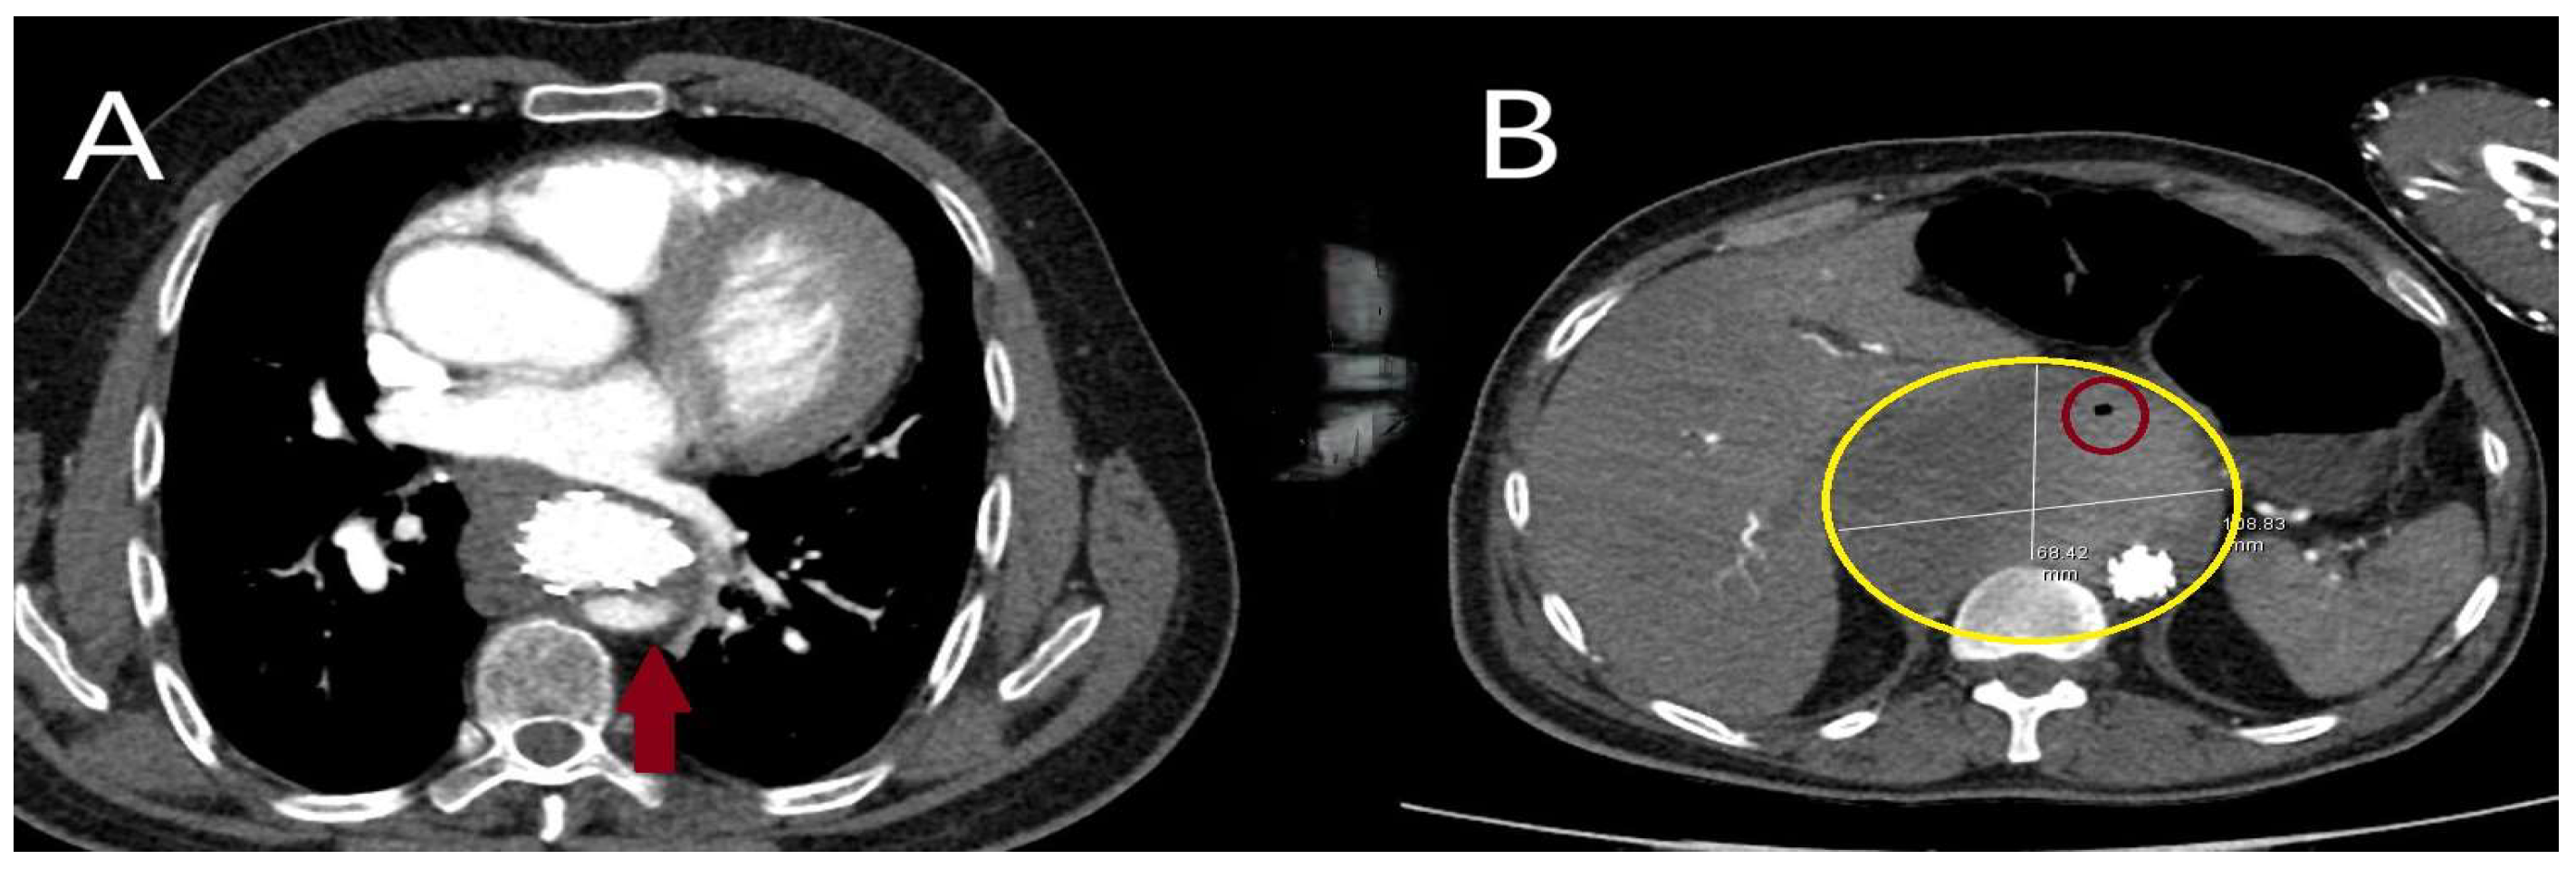

5.2.3. Computed Tomography